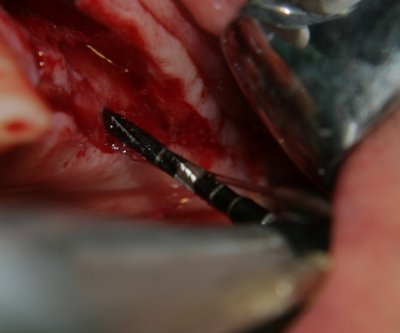

Имплантатът е поставен. За непрофесионалисти снимката е изключително зловеща - кръв, инструменти, зъби и нагледна човешка анатомия... В действителност обаче поставянето на зъбни импланти е една от най-атравматичните операции в областта на Оралната и Лицево - челюстната хирургия: не се отнема никакъв костен обем (както е при екстракцията на един ретиниран мъдрец например), поставя се стерилно тяло в костта, не се отпрепарират тъканите нашироко (както е при операцията на киста, остеомиелит или, недай боже, тумор). Изключително радко се налага антибиотичен прием постоперативно - обикновено при извършване на костна пластика в голям обем. Повече информация за приложението на антибиотиците в имплантологията прочетете тук...